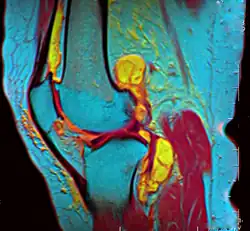

In addition, variants of false colors such as pseudocolors, density slicing, and choropleths are used for information visualization of either data gathered by a single grayscale channel or data not depicting parts of the electromagnetic spectrum (e.g. elevation in relief maps or tissue types in magnetic resonance imaging).

A pseudocolor image (sometimes styled pseudo-color or pseudo color) is derived from a grayscale image by mapping each intensity value to a color according to a table or function.[11] Pseudo color is typically used when a single channel of data is available (e.g. temperature, elevation, soil composition, tissue type, and so on), in contrast to false color which is commonly used to display three channels of data.[4]

Depending on the table or function used and the choice of data sources, pseudocoloring may increase the information contents of the original image, for example adding geographic information, combining information obtained from infrared or ultra-violet light, or other sources like MRI scans.[13]